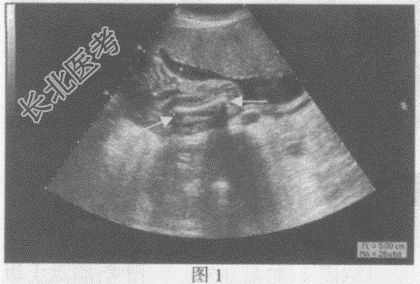

- 单项选择题请指出下图箭头所指的是胎儿哪个部位:

A、图1:胎儿股骨长径,图2:脚

B、图1:胎儿胫骨长径,图2:手

C、图1:胎儿肱骨长径,图2:面部

D、图1:胎儿桡骨长径,图2:颈部

E、图1:胎儿桡骨长径,图2:脊柱